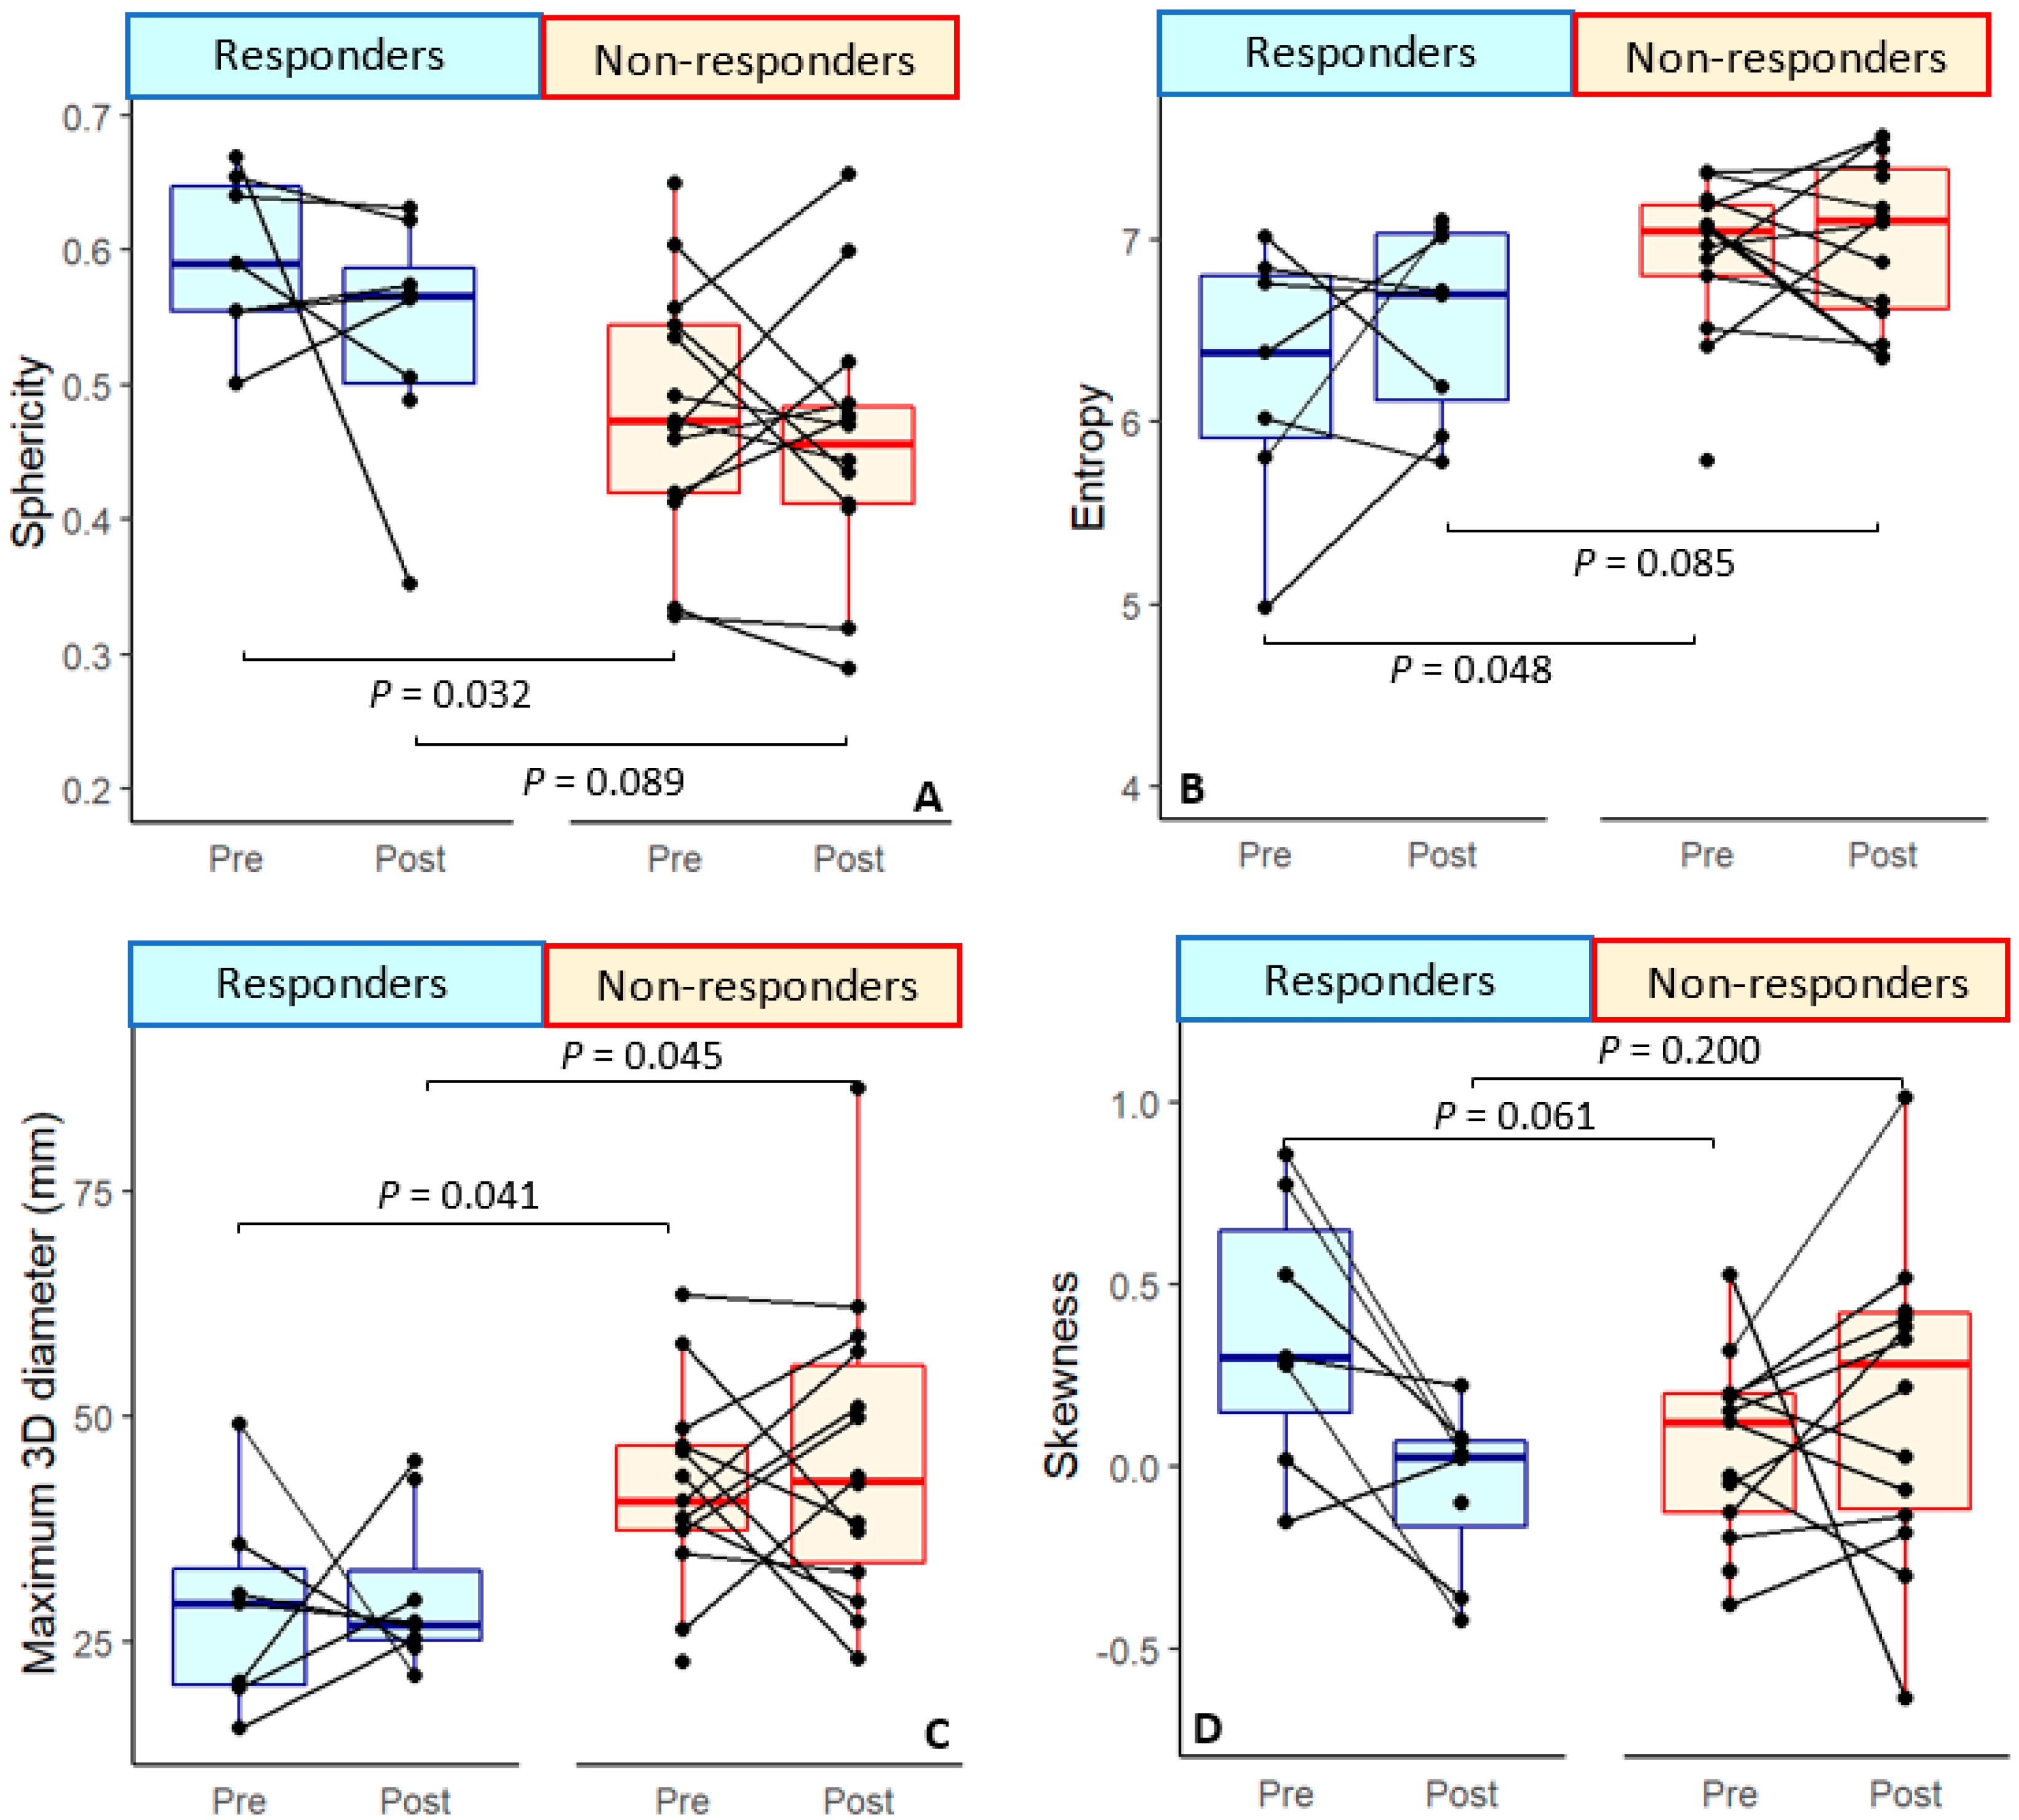

| Entropy | 6.26 ± 0.71 * | 0.22 ± 0.74 | 6.56 ± 0.53 | 6.89 ± 0.41 * | −0.06 ± 0.45 | 6.99 ± 0.44 |

| Skewness | 0.37 ± 0.37 | −0.42 ± 0.36 | −0.06 ± 0.22 | 0.08 ± 0.25 | 0.02 ± 0.47 | 0.15 ± 0.41 |

| Sphericity | 0.60 ± 0.06 * | −0.05 ± 0.13 | 0.54 ± 0.09 | 0.49 ± 0.09 * | −0.002 ± 0.09 | 0.46 ± 0.09 |

| 3D diameter (cm) | 2.86 ± 1.15 * | −0.01 ± 1.70 | 3.03 ± 0.88 * | 4.15 ± 1.09 * | −0.08 ± 1.39 | 4.51 ± 1.64 * |

| Entropy | 0.048 * | −1.43 ± 0.69 | 0.033 * | −6.32 ± 2.97 | 0.285 | 0.067 | ||||

| Skewness | 0.061 | 0.066 | 0.200 | |||||||

| Sphericity | 0.032 * | 1.84 ± 0.86 | 0.024 * | 2.57 ± 1.138 | 0.327 | 0.089 | ||||

| 3D diameter (cm) | 0.041 * | −1.47 ± 0.72 | 0.034 * | −2.29 ± 1.08 | 0.913 | 0.045 * | −1.75 ± 0.87 | 0.040 * | −1.88 ± 0.91 | |